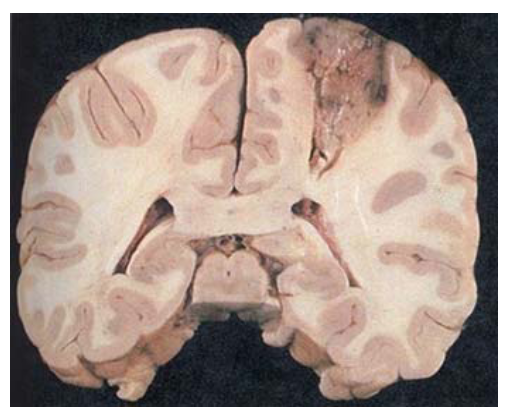

What pathology is shown in the provided images?

Advanced stage PML

large areas of cerebral white matter have depressed, cavitated areas w/ granular appearance (black open arrow)